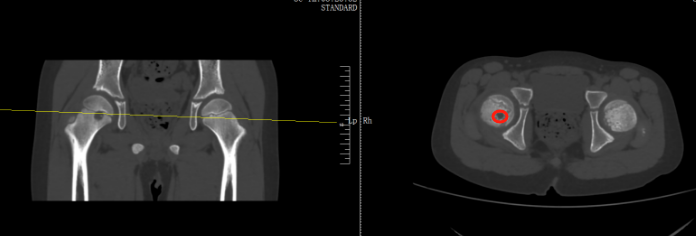

当地医师会诊为右股骨近端占位,怀疑里面可能长了肿瘤。扬扬姆妈听到医师的话心里直发怵,夫妻两东说念主又马不休蹄带孩子来到了骨科病院进一步查验,扬扬被确诊为右股骨近端肿瘤。

好在从影像上来看,初步沟通是偏良性。在跟家长盘考事后,医师为扬扬膨胀了前侧入路右侧股骨头钻取刮除、取自体髂骨骨移植术,手术顺利切除病灶,并补上了股骨的“破绽”。